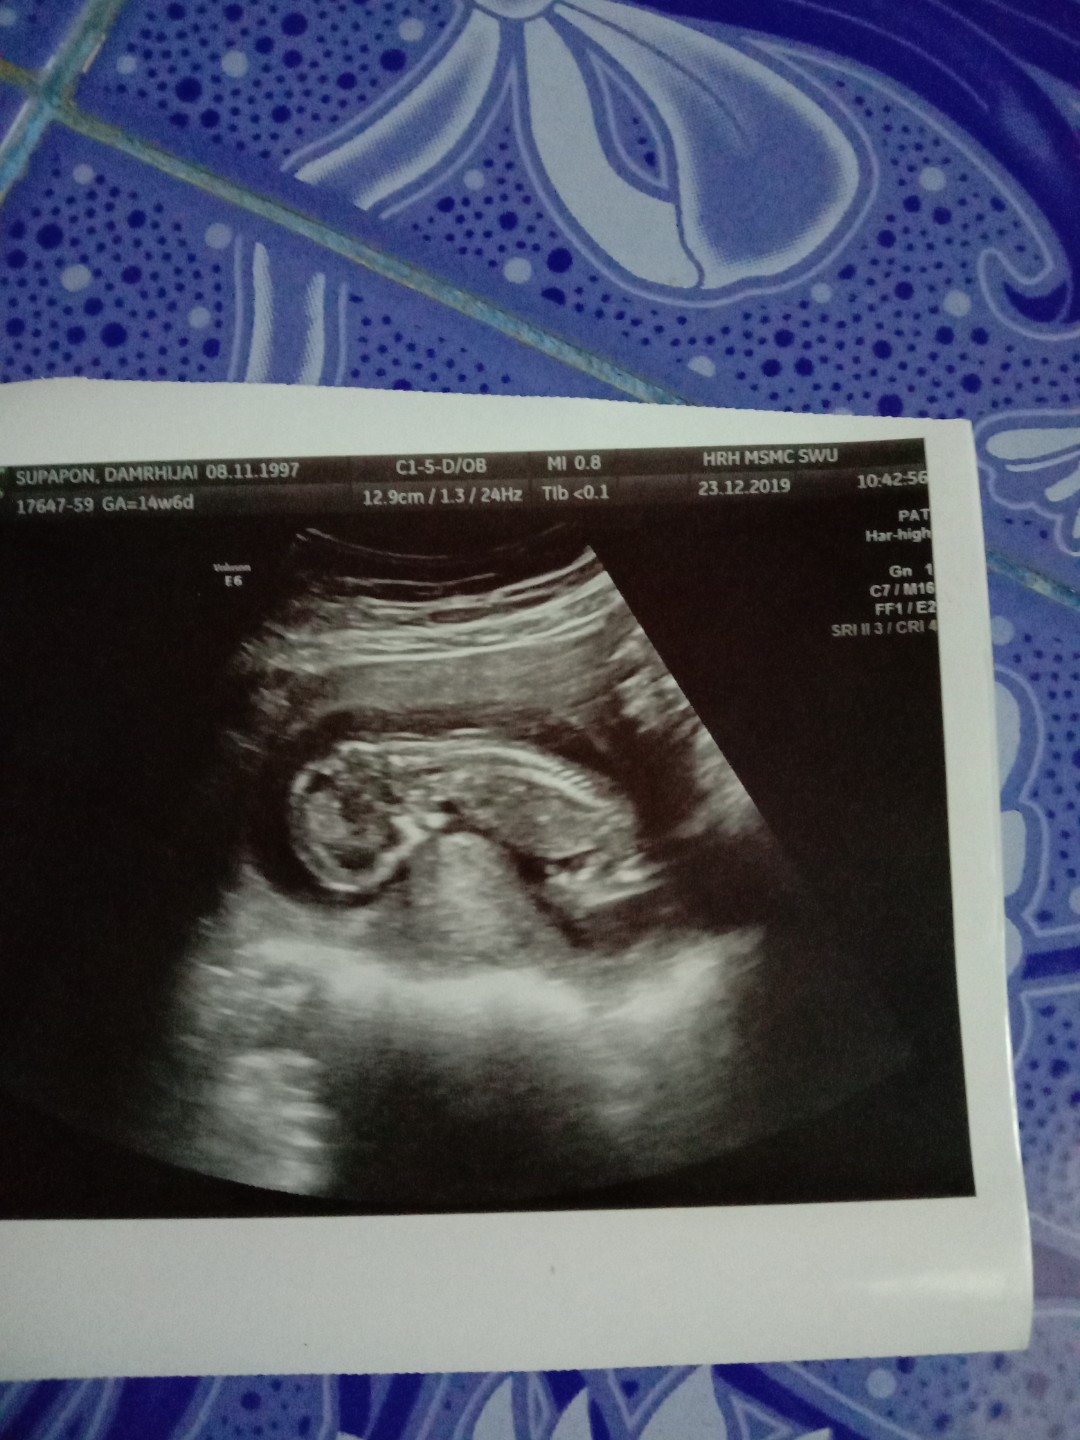

14w6d คะ ตอนนี้16w3d คะ